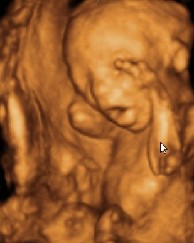

一個21周大的胎兒超聲波圖像(左)及根據超聲波圖像制成的21周大的胎兒模型(右)

據英國《每日郵報》6月26日報道,正在英國皇家藝術學院學習設計的博士生、來自巴西的豪爾赫·洛佩斯的這項研究成果將于26日在英國皇家藝術學院舉行的展覽會上進行展示。該研究成果是利用快速成型技術(rapid prototyping),將超聲波和核磁共振成像的數據進行轉換并制成與腹中胎兒一般大小的石膏模型。